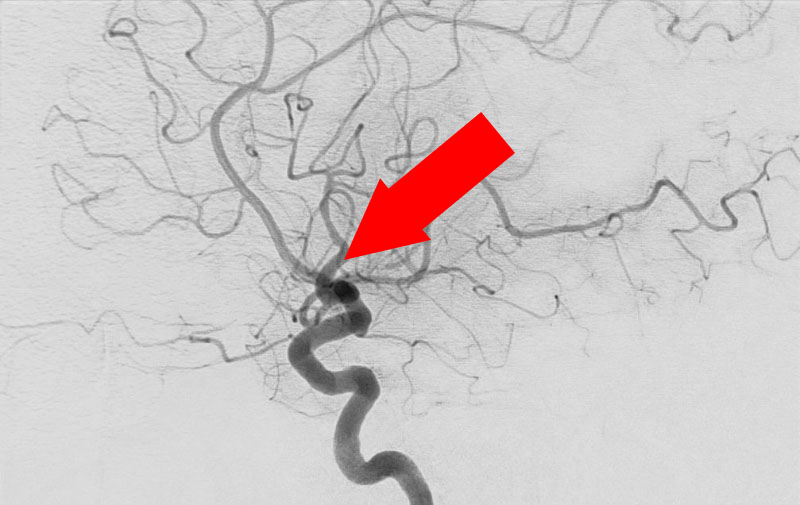

'22年7月

前交通動脈瘤

60代

大阪府の病院

No.1251 手術前

No.1251 手術中

No.1251 手術後